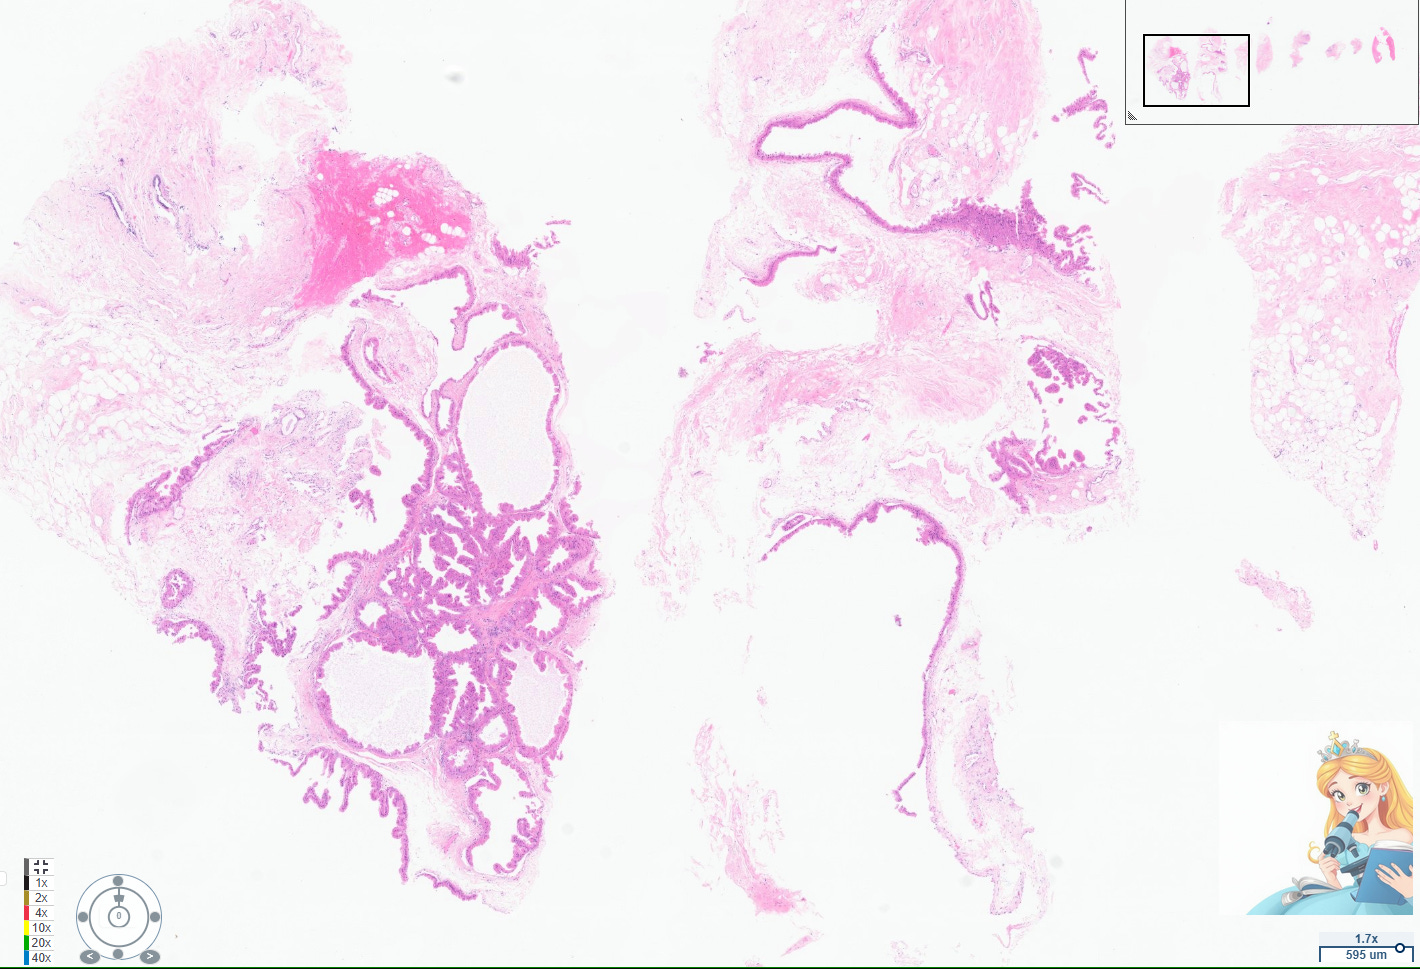

Apocrine cysts are a common manifestation of fibrocystic change in the breast, particularly in women over 25 years old. These cysts are lined by apocrine cells, which are characterized by abundant eosinophilic granular cytoplasm, round nuclei with pale chromatin, and prominent nucleoli. The apocrine lining may be cuboidal or columnar, and the cells typically have a low nuclear-to-cytoplasmic ratio and prominent apical snouts, reflecting apocrine secretion.[1-2]

Apocrine metaplasia is considered a benign, non-proliferative change and is frequently seen in the context of breast cysts, often as part of the broader spectrum of fibrocystic change. It is so prevalent after age 25 that it is regarded as a normal histologic finding in adult breast tissue.[2-3] The presence of apocrine metaplasia in cysts does not, by itself, confer an increased risk of malignancy, and these cysts are considered a hallmark of benign breast disease.[1-2][4]

Abundant apocrine cystic change has been termed cystic papillary apocrine metaplasia by pathologists. However, using this term diagnostically can be confusing to radiologists who are concerned that the term “papillary” warrants consideration for excision. Always rule out a papilloma with apocrine changes when evaluating this particular type of apocrine changes, which can appear architecturally complex.